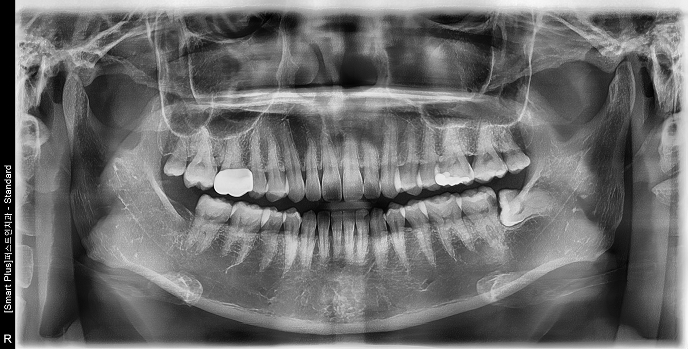

• STEP 02 X-ray 확인

뿌리 형태와 위치, 신경·상악동과의 거리를 파악해 안전한 발치 계획을 세웁니다.

• 20대 남성 | #38 사랑니발치 | 치료기간 당일

Before 2022.06.24

After 2022.06.24

• 30대 여성 | #38 사랑니발치 | 치료기간 당일

Before 2025.03.06

After 2025.03.06